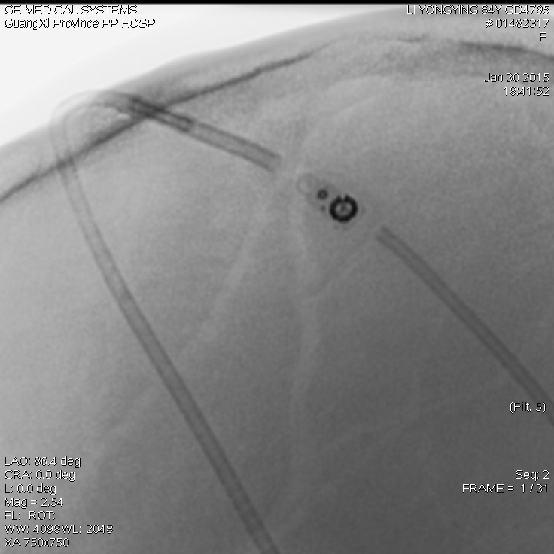

2015-1-30 DSA